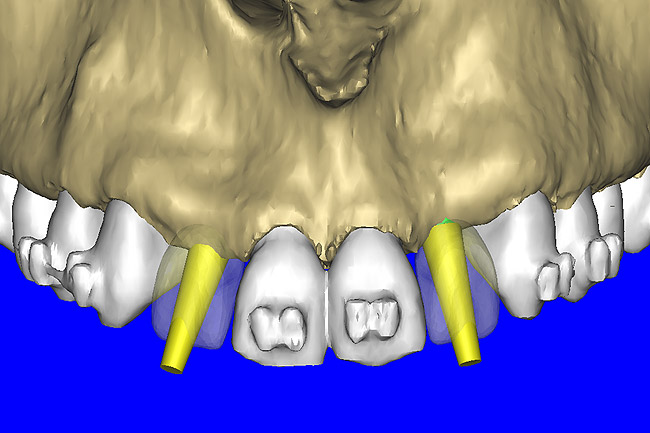

After the basic plan had been established, it was re-evaluated using interactive 3D images. The reconstructed 3D view of the maxilla clearly illustrated the extent of the bilateral facial concavities, and the root eminences of the adjacent and posterior teeth (Figure 7A). The placement of the virtual implants then was evaluated to ensure that the facial cortical plate was not perforated (Figure 7B). The implants were labeled individually as “7” and “10,” with the simulated yellow abutment projection indicating the facial-lingual inclination through the bone to the level above the incisal edge of adjacent teeth. The ability to gain a better understanding of these individual root forms can not be underestimated. The dental literature has suggested certain parameters for placing implants near teeth and implants next to other implants. However, there is little scientific 3D documentation to support these suggested rules.5-10 The use of an interactive treatment-planning software application permits closer scrutiny of previously difficult-to-visualize areas, and can now be used to redefine perceptions of spatial positioning of implants, especially when in close proximity to natural tooth roots, vital anatomy, and adjacent implants.27-29

Figure 7a  The 3D reconstruction showed (A) the facial concavities and root eminences, and allowed (B) for evaluation of virtual implant placement to ensure the facial cortical plate was not perforated.

Figure 7a

Figure 7b  The 3D reconstruction showed (A) the facial concavities and root eminences, and allowed (B) for evaluation of virtual implant placement to ensure the facial cortical plate was not perforated.

Figure 7b